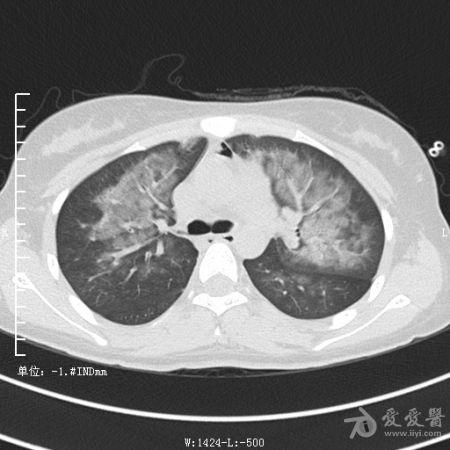

典型支气管扩张及肺水肿CT片

典型支气管扩张肺水肿